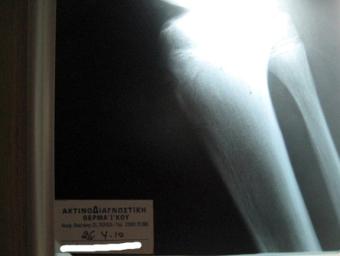

Σύνδρομο Osgood-Schlatter σε νεαρό αθλητή |

Ακτινογραφία 26-4-2010 |